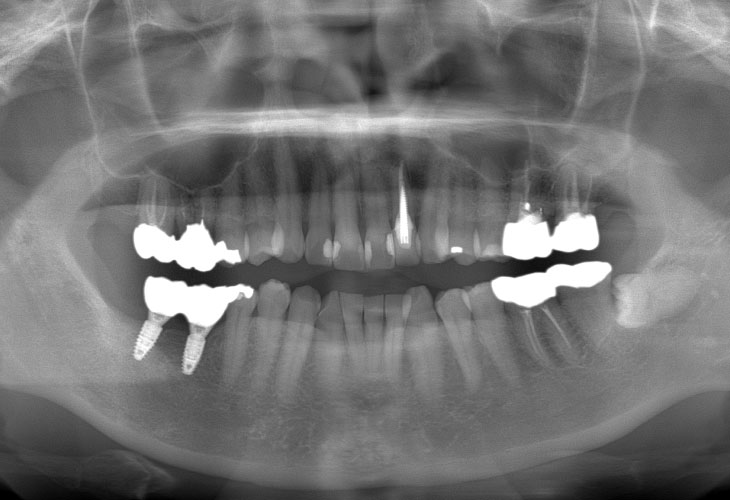

AFTER

右下奥歯の歯が無い。インプラント治療をしたい。

右下臼歯部欠損

インプラント(右下6・7)

インプラント: 4ヶ月/6回

オールセラミック、E-MAX CAD: 4ヶ月/6回

インプラント: 700,000円

オールセラミック、E-MAX CAD: 269,500円

合計 969,500円

定期的なメインテナンスを行わない場合、インプラントが脱落する可能性があります。被せ物は経年的な劣化で欠ける可能性があります。